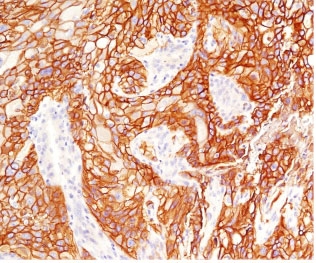

IHC testing of FFPE human lung squamous cell carcinoma with EGFR antibody (clone ERB68-1). Required HIER: boiling tissue sections in pH 9 10mM Tris with 1mM EDTA for 10-20 min.